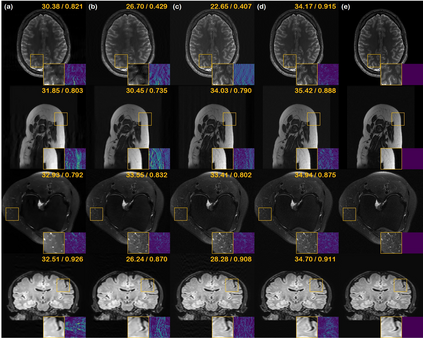

Score-based diffusion models provide a powerful way to model images using the gradient of the data distribution. Leveraging the learned score function as a prior, here we introduce a way to sample data from a conditional distribution given the measurements, such that the model can be readily used for solving inverse problems in imaging, especially for accelerated MRI. In short, we train a continuous time-dependent score function with denoising score matching. Then, at the inference stage, we iterate between numerical SDE solver and data consistency projection step to achieve reconstruction. Our model requires magnitude images only for training, and yet is able to reconstruct complex-valued data, and even extends to parallel imaging. The proposed method is agnostic to sub-sampling patterns, and can be used with any sampling schemes. Also, due to its generative nature, our approach can quantify uncertainty, which is not possible with standard regression settings. On top of all the advantages, our method also has very strong performance, even beating the models trained with full supervision. With extensive experiments, we verify the superiority of our method in terms of quality and practicality.